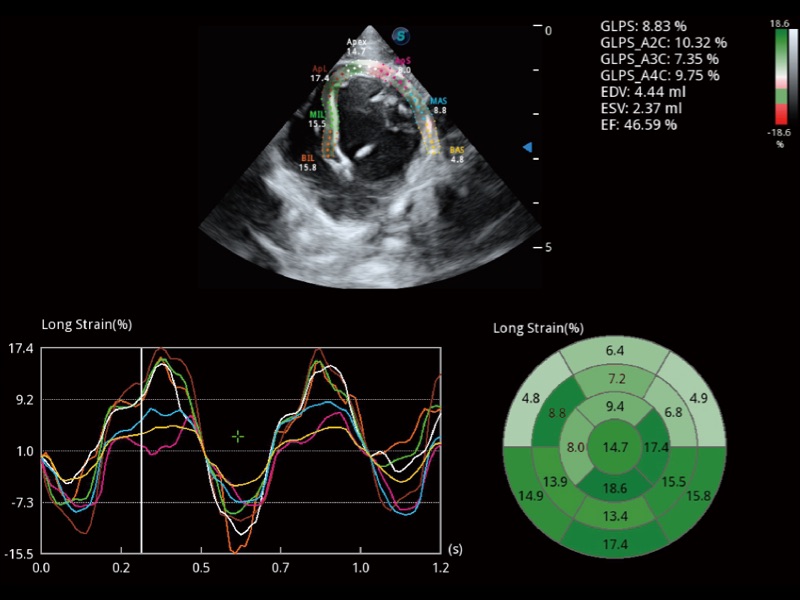

能够基于左心室壁追踪和辛普森法,自动计算射血分数,支持多个可移动点描迹,与手动测量相比,极大节省了动物医生的时间和精力。

具备多种协议可选,同时支持17阶段划分法和专业的SE报告。

实时用颜色表示心肌组织运动,观察和定量组织的运动情况,对快速检测与评估心肌的灌注和活性、电传导及心肌收缩和舒张功能等均能提供重要的诊断信息。

当心脏测量结果超出正常范围时,可实时预警提示动物医生,减少疾病漏诊概率。